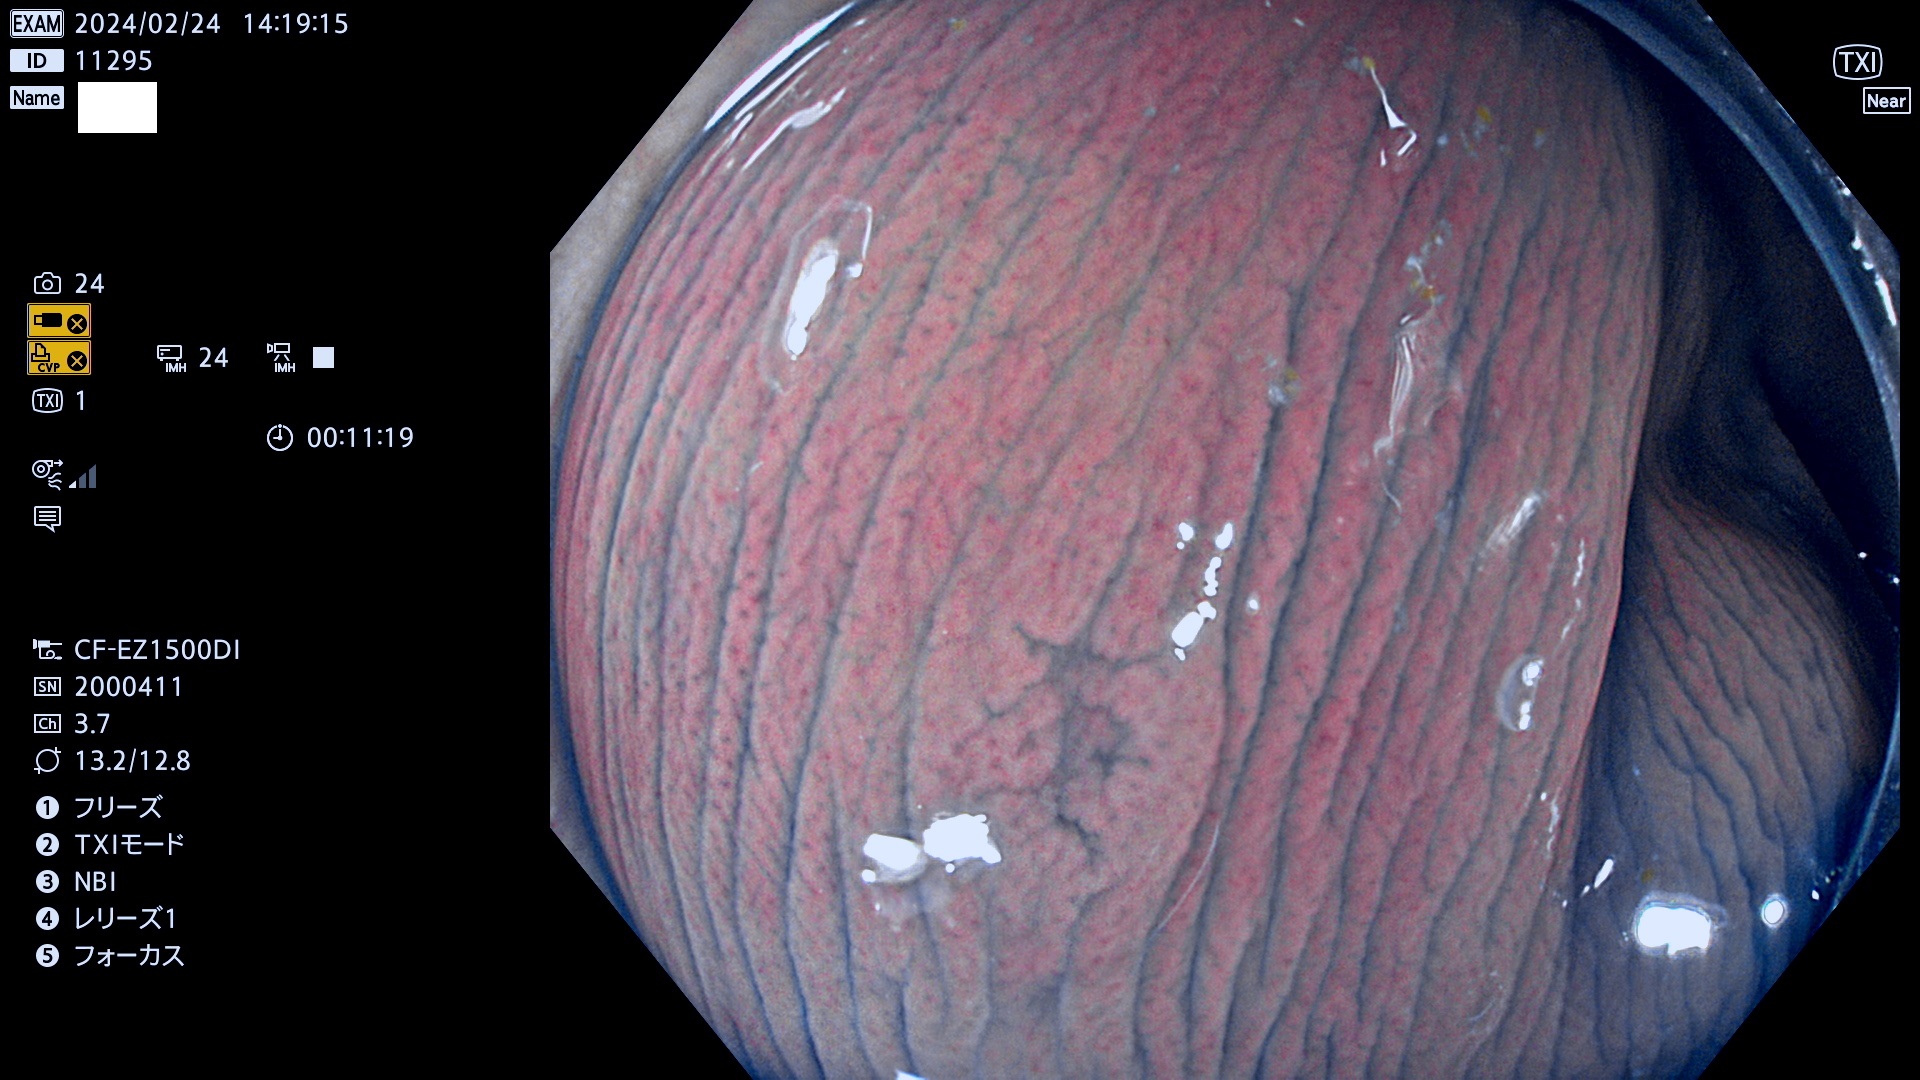

表面型腺腫(Flat Adenoma)の中で、完全に平坦な物をUb、陥凹している物をUcと呼びます。平坦隆起型(Ua)よりも、発見が難しく危険な病変です。

毎週の検査(木・金・土・日)に発見されたUb、Uc型・腺腫を、その週の日曜の夜にUPし1週間、提示します。

抽出の対象期間 2024年2月22日(木)〜2月25(日)の5日間(50件の検査)5件 (5/50=10%)